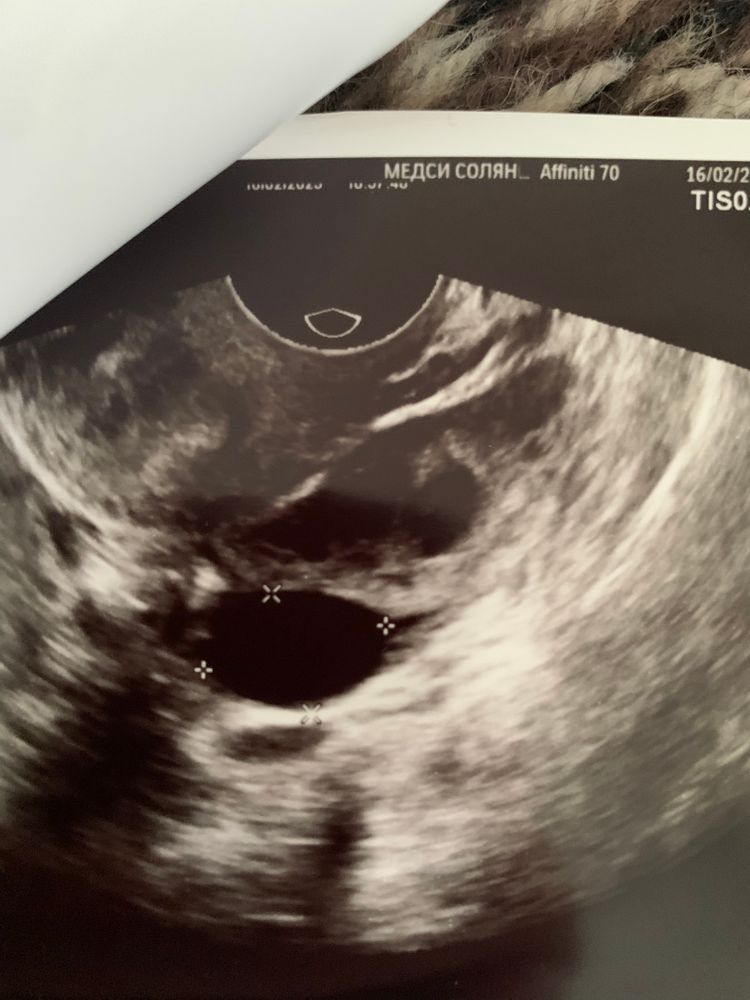

Ana , вот такая картина узи. На дф не похоже?

Вероника, похоже уже на разорвавшихся фолликул,может это процесс овуляции как раз.

Вероника, ну день цикла думаю влияет приблизительно. Похоже больше на саму овуляцию в этот раз,его как будто разрывает уже,или может перепутал запись и надо было написать жёлтое тело,края в этот раз не такие четкие ,а размытые. Мне в этот раз тоже узистка нагородили, тоже скоро спрашивать начну)